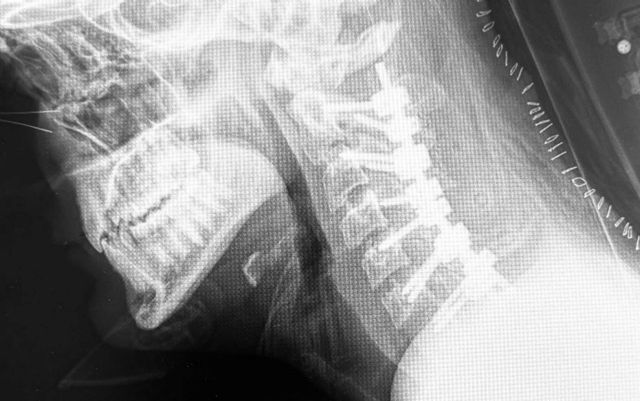

En este artículo, el Dr. Botella-Asunción, como experto en el tratamiento y cirugía de columna mínimamente invasiva, habla de la cifosis post-laminectomía cervical.

La cifosis post-laminectomía cervical es una curvatura anormal hacia adelante de la columna cervical (cuello) que puede ocurrir después de una laminectomía, que es un tipo de cirugía de columna. Esta condición puede resultar de la eliminación de parte de la lámina, que es una estructura ósea que cubre y protege la médula espinal, lo que puede alterar la estabilidad y la alineación de la columna vertebral. La gravedad de la cifosis y los síntomas asociados pueden variar y, en consecuencia, las estrategias de tratamiento también

Fusión Espinal: Unir dos o más vértebras utilizando injertos óseos y/o dispositivos de fijación como tornillos y barras para estabilizar y corregir la alineación de la columna vertebral.